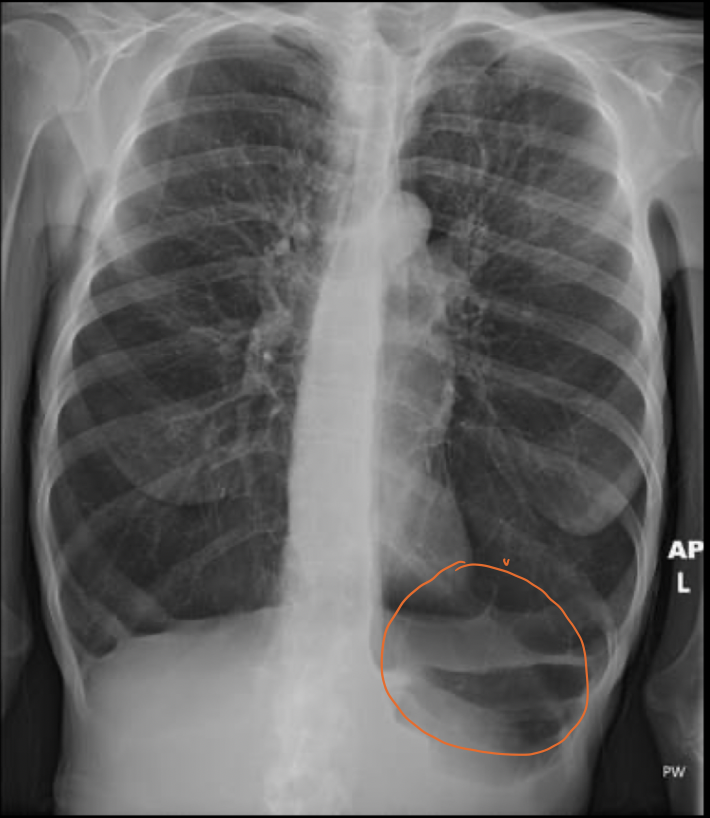

Q

Esta aplanamiento del diafragma con sobreposición del pulmón con el colon nos habla de que enfermedad

A

Enfisema pulmonar